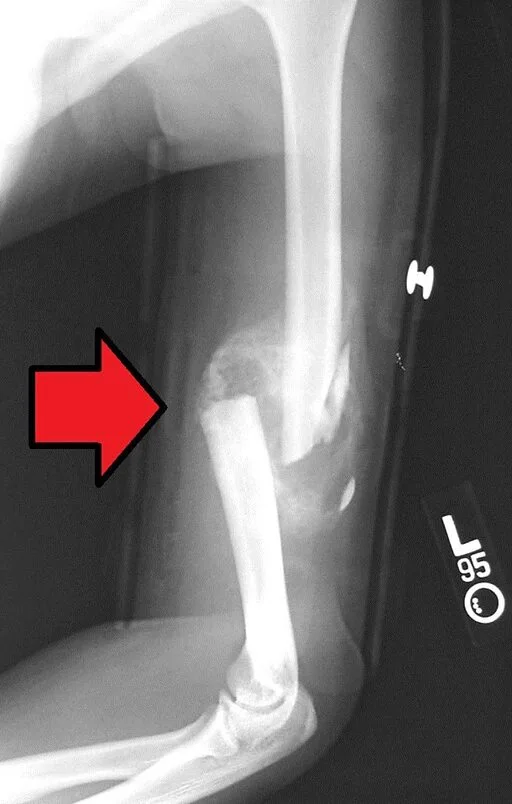

How Broken Bones Heal, do bones grow back

How to Heal Broken Bones? Learn the answer to the question.